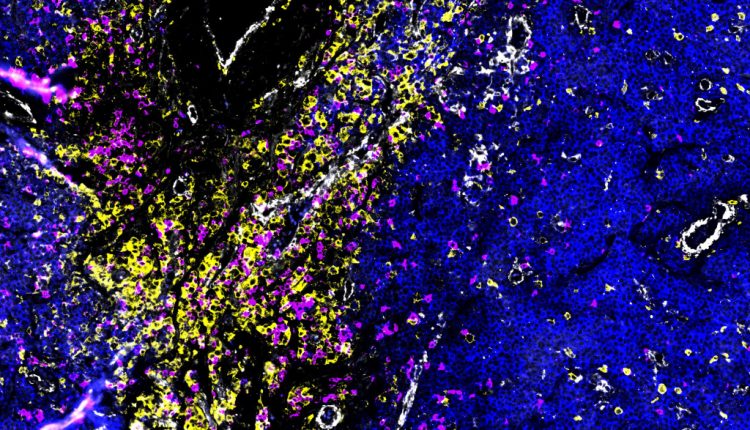

Ansammlung verschiedener Arten von Immunzellen in einem aus dem Knochen herausgebrochenen Myelomherd: T-Zellen und Natürliche Killerzellen sind pink, Makrophagen gelb dargestellt. Die umgebenden Myelomzellen erscheinen blau. Die weißen Strukturen sind Blutgefäße. Bild: Dr. Johanna Wagner, DKFZ und NCT Heidelberg, mit Hilfe räumlicher Multi-Omics Methoden aufgenommen.